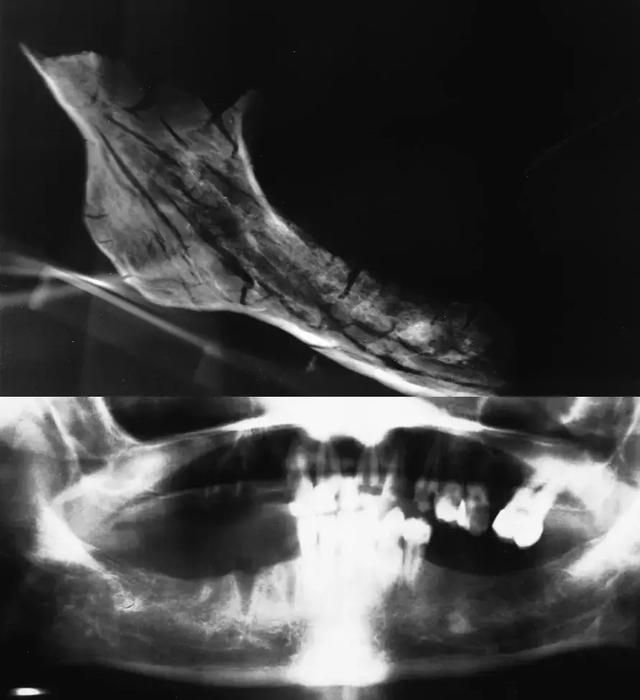

幸好哈里于1977-1981年间在医院拍摄过几次影像片,其中包括一次1981年拍摄的口腔全景片,骨骼残片里有一个下颌骨的右侧部分,包括下颌体和下颌支,其牙槽窝位置与哈里生前所摄口腔全景片所反映的牙槽窝位置相一致;而且通过对这块残破的下颌骨进行X光摄片,发现一块高密度影,其大小、位置与哈里生前所摄口腔全景片相一致,同时,沿着下颌下缘与下颌管的一些松质骨的区域也是相匹配的,包括颏孔所在位置也是相一致的。

总之,这块下颌骨残片与1981年哈里所摄的口腔全景片没有不一致的地方。如图所示:

图25 上为现场收集到的那块缺损的下颌骨拍摄的X光片,下为哈里生前所摄口腔全景片。图源:参考资料2